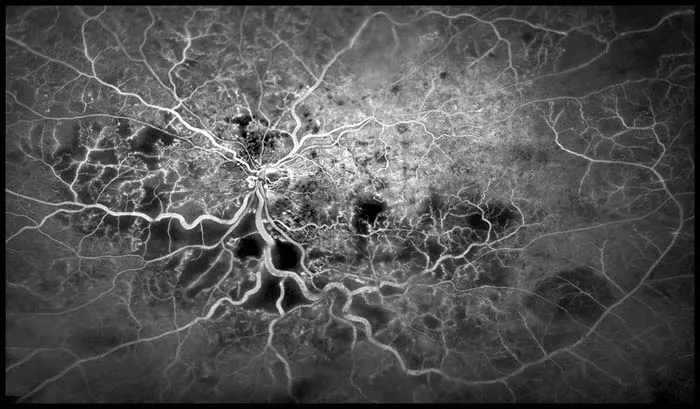

رگهای خونی چشم

نکتهی بسیار جالب دربارهی این تصویر این است که وقتی به آن نگاه میکنیم، اصلا یاد چشم نمیافتیم. این تصویر شبیه یک چشمانداز هوایی از یک شهر یا تصویر تلسکوپی از یک کهکشان دور به نظر میرسد.

این عکس با تصویربرداری از رگهای خونی شبکیه تهیه شده که به شکل تار عنکبوت سفید دیده میشوند.